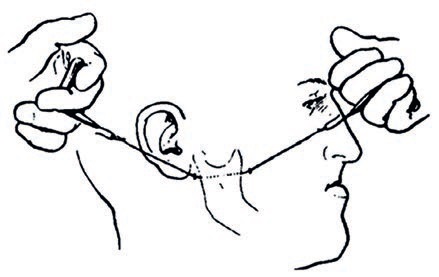

W niniejszej pracy kazuistycznej przedstawiono przypadek dorosłego pacjenta z ciężką szkieletową wadą zgryzu klasy III, z ewidentnym niedorozwojem szczęki i nadmiernie rozwiniętą żuchwą, co powodowało zgryz krzyżowy przedni i tylny, a także przesu...

Słowa kluczowe: chirurgia ortognatyczna, obustronna strzałkowa osteotomia żuchwy, chirurgia twarzoczaszki, staw skroniowo-żuchwowy, zaburzenia stawu skroniowo-żuchwowego Keywords: orthognathic surgery; bilateral sagittal split osteotomy; craniofac...